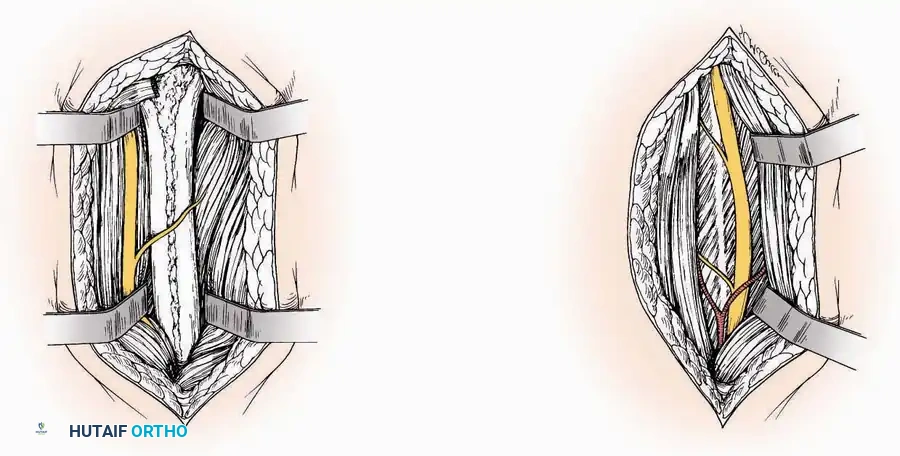

Anterior Approach

Indications: Total ankle arthroplasty (TAA), anterior ankle arthrodesis, and excision of anterior tibial/talar osteophytes (anterior impingement).

Surgical Technique:

* Incision: Make a 10 to 15 cm longitudinal incision over the anterior aspect of the ankle, centered exactly midway between the medial and lateral malleoli.

* Superficial Dissection: Incise the superficial fascia. Identify and protect the superficial peroneal nerve branches laterally and the saphenous nerve medially.

* Internervous Plane: The deep dissection exploits the plane between the Extensor Hallucis Longus (EHL) tendon (innervated by the deep peroneal nerve) and the Extensor Digitorum Longus (EDL) tendons (also innervated by the deep peroneal nerve).

* Neurovascular Bundle: Incise the extensor retinaculum. Carefully identify the anterior tibial artery and the deep peroneal nerve, which typically lie between the EHL and EDL, or directly deep to the EHL. Retract the neurovascular bundle laterally with the EDL, or medially with the EHL, depending on the specific anatomical variant encountered (lateral retraction is most common).

* Capsulotomy: Incise the anterior joint capsule longitudinally. Elevate the capsule subperiosteally from the anterior tibia and the talar neck to expose the entire tibiotalar articulation.